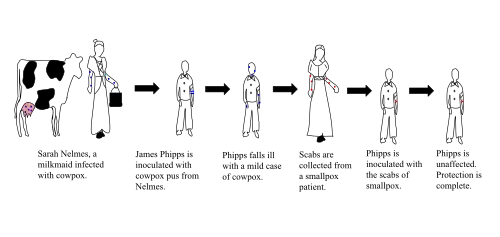

The smallpox vaccine is used to prevent smallpox infection caused by the variola virus.[10] It is the first vaccine to have been developed against a contagious disease. In 1796, British physician Edward Jenner demonstrated that an infection with the relatively mild cowpox virus conferred immunity against the deadly smallpox virus. Cowpox served as a natural vaccine until the modern smallpox vaccine emerged in the 20th century. From 1958 to 1977, the World Health Organization (WHO) conducted a global vaccination campaign that eradicated smallpox,[10] making it the only human disease to be eradicated. Although routine smallpox vaccination is no longer performed on the general public, the vaccine is still being produced for research,[10] and to guard against bioterrorism, biological warfare, and mpox.[11][12]

Edward Jenner was born in Berkeley, England. As a young child, Jenner was variolated with the other schoolboys through parish funds, but nearly died due to the seriousness of his infection. Fed purgative medicine and going through the bloodletting process, Jenner was put in one of the variolation stables until he recovered.[91] At the age of 13, he was apprenticed to apothecary Daniel Ludlow and later surgeon George Hardwick in nearby Sodbury. He observed that people who caught cowpox while working with cattle were known not to catch smallpox. Jenner assumed a causal connection but the idea was not taken up at that time. From 1770 to 1772 Jenner received advanced training in London at St. George's Hospital and as the private pupil of John Hunter, then returned to set up practice in Berkeley.[92]

Perhaps there was already an informal public understanding of some connection between disease resistance and working with cattle. The "beautiful milkmaid" seems to have been a frequent image in the art and literature of this period. But it is known for certain that in the years following 1770, at least six people in England and Germany (Sevel, Jensen, Jesty 1774, Rendall, Plett 1791) tested successfully the possibility of using the cowpox vaccine as an immunization for smallpox in humans.[93]

Jenner sent a paper reporting his observations to the Royal Society in April 1797. It was not submitted formally and there is no mention of it in the Society's records. Jenner had sent the paper informally to Sir Joseph Banks, the Society's president, who asked Everard Home for his views. Reviews of his rejected report, published for the first time in 1999, were skeptical and called for further vaccinations.[94] Additional vaccinations were performed and in 1798 Jenner published his work entitled An Inquiry into the Causes and Effects of the Variolae Vaccinae, a disease discovered in some of the western counties of England, particularly Gloucestershire and Known by the Name of Cow Pox.[73][95][96] It was an analysis of 23 cases including several individuals who had resisted natural exposure after previous cowpox. It is not known how many Jenner vaccinated or challenged by inoculation with smallpox virus; e.g. Case 21 included 'several children and adults'. Crucially all of at least four whom Jenner deliberately inoculated with smallpox virus resisted it. These included the first and last patients in a series of arm-to-arm transfers. He concluded that cowpox inoculation was a safe alternative to smallpox inoculation, but rashly claimed that the protective effect was lifelong. This last proved to be incorrect.[97] Jenner also tried to distinguish between 'True' cowpox which produced the desired result and 'Spurious' cowpox which was ineffective and/or produced severe reaction. Modern research suggests Jenner was trying to distinguish between effects caused by what would be recognised as a non-infectious vaccine, a different virus (e.g. paravaccinia/milker's nodes), or contaminating bacterial pathogens. This caused confusion at the time, but would become important criteria in vaccine development.[98] A further source of confusion was Jenner's belief that fully effective vaccine obtained from cows originated in an equine disease, which he mistakenly referred to as grease. This was criticised at the time but vaccines derived from horsepox were soon introduced and later contributed to the complicated problem of the origin of vaccinia virus, the virus in present-day vaccine.[99]: 165–78

The question of who first tried cowpox inoculation/vaccination cannot be answered with certainty. Most, but still limited, information is available for Benjamin Jesty, Peter Plett and John Fewster. In 1774 Jesty, a farmer of Yetminster in Dorset, observing that the two milkmaids living with his family were immune to smallpox, inoculated his family with cowpox to protect them from smallpox. He attracted a certain amount of local criticism and ridicule at the time then interest waned. Attention was later drawn to Jesty, and he was brought to London in 1802 by critics jealous of Jenner's prominence at a time when he was applying to Parliament for financial reward.[118] During 1790–92 Peter Plett, a teacher from Holstein, reported limited results of cowpox inoculation to the Medical Faculty of the University of Kiel. However, the Faculty favoured variolation and took no action.[119] John Fewster, a surgeon friend of Jenner's from nearby Thornbury, discussed the possibility of cowpox inoculation at meetings as early as 1765. He may have done some cowpox inoculations in 1796 at about the same time that Jenner vaccinated Phipps. However, Fewster, who had a flourishing variolation practice, may have considered this option but used smallpox instead. He thought vaccination offered no advantage over variolation, but maintained friendly contact with Jenner and certainly made no claim of priority for vaccination when critics attacked Jenner's reputation.[120] It seems clear that the idea of using cowpox instead of smallpox for inoculation was considered, and actually tried in the late 18th century, and not just by the medical profession. Therefore, Jenner was not the first to try cowpox inoculation. However, he was the first to publish his evidence and distribute vaccine freely, provide information on selection of suitable material, and maintain it by arm-to-arm transfer. The authors of the official World Health Organization (WHO) account Smallpox and its Eradication assessing Jenner's role wrote:[19]: 264